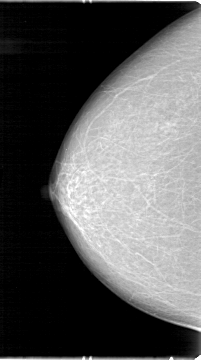

D_4042_1.RIGHT_MLO

RIGHT_CC LINES 5386 PIXELS_PER_LINE 3001 BITS_PER_PIXEL 12 RESOLUTION 43.5 NON_OVERLAY

RIGHT_MLO LINES 5206 PIXELS_PER_LINE 2806 BITS_PER_PIXEL 12 RESOLUTION 43.5 NON_OVERLAY